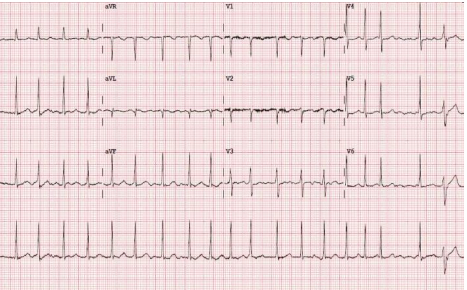

Um jovem médico resolve fazer, pela primeira vez, um plantão noturno na emergência. Na madrugada, uma senhora de 75 anos, hipertensa e diabética dá entrada com queixa de dispneia e taquicardia. Ao exame clínico, observou-se FC = 122 bpm, PA = 140x90mmHg, ausculta pulmonar limpa, discreto edema de membros inferiores e Sat. O2 95%. Trouxe um ecocardiograma recente que mostrou diâmetro ventricular esquerdo normal, aumento discreto de átrio esquerdo, hipertensão pulmonar discreta e FEVE = 62%.

O médico solicitou os seguintes exames a seguir:

Leia o caso clínico que segue para responder às questões de 32 a 36.

Um jovem médico resolve fazer, pela primeira vez, um plantão noturno na emergência. Na madrugada, uma senhora de 75 anos, hipertensa e diabética dá entrada com queixa de dispneia e taquicardia. Ao exame clínico, observou-se FC = 122 bpm, PA = 140x90mmHg, ausculta pulmonar limpa, discreto edema de membros inferiores e Sat. O2 95%. Trouxe um ecocardiograma recente que mostrou diâmetro ventricular esquerdo normal, aumento discreto de átrio esquerdo, hipertensão pulmonar discreta e FEVE = 62%.

O médico solicitou os seguintes exames a seguir:

Leia o caso clínico que segue para responder às questões de 32 a 36.

Um jovem médico resolve fazer, pela primeira vez, um plantão noturno na emergência. Na madrugada, uma senhora de 75 anos, hipertensa e diabética dá entrada com queixa de dispneia e taquicardia. Ao exame clínico, observou-se FC = 122 bpm, PA = 140x90mmHg, ausculta pulmonar limpa, discreto edema de membros inferiores e Sat. O2 95%. Trouxe um ecocardiograma recente que mostrou diâmetro ventricular esquerdo normal, aumento discreto de átrio esquerdo, hipertensão pulmonar discreta e FEVE = 62%.

O médico solicitou os seguintes exames a seguir:

Em relação ao ECG,

Leia o caso clínico que segue para responder às questões de 32 a 36.

Um jovem médico resolve fazer, pela primeira vez, um plantão noturno na emergência. Na madrugada, uma senhora de 75 anos, hipertensa e diabética dá entrada com queixa de dispneia e taquicardia. Ao exame clínico, observou-se FC = 122 bpm, PA = 140x90mmHg, ausculta pulmonar limpa, discreto edema de membros inferiores e Sat. O2 95%. Trouxe um ecocardiograma recente que mostrou diâmetro ventricular esquerdo normal, aumento discreto de átrio esquerdo, hipertensão pulmonar discreta e FEVE = 62%.

O médico solicitou os seguintes exames a seguir:

Leia o caso clínico que segue para responder às questões de 32 a 36.

Um jovem médico resolve fazer, pela primeira vez, um plantão noturno na emergência. Na madrugada, uma senhora de 75 anos, hipertensa e diabética dá entrada com queixa de dispneia e taquicardia. Ao exame clínico, observou-se FC = 122 bpm, PA = 140x90mmHg, ausculta pulmonar limpa, discreto edema de membros inferiores e Sat. O2 95%. Trouxe um ecocardiograma recente que mostrou diâmetro ventricular esquerdo normal, aumento discreto de átrio esquerdo, hipertensão pulmonar discreta e FEVE = 62%.

O médico solicitou os seguintes exames a seguir:

Qual é o diagnóstico para o eletrocardiograma?